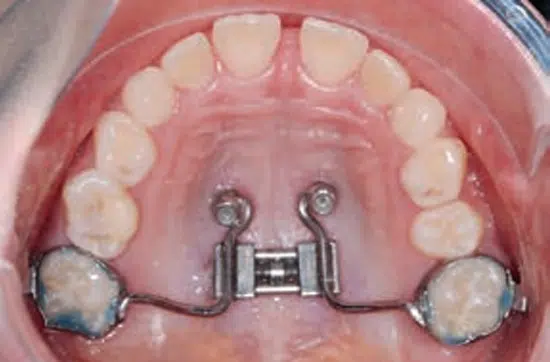

El MARPE es un procedimiento ortodóntico avanzado que utiliza mini tornillos para asistir en la expansión rápida del paladar superior.

Este tratamiento está diseñado para corregir deficiencias maxilares mediante una expansión esquelética, creando más espacio y promoviendo ajustes naturales en la forma y tamaño del maxilar superior.